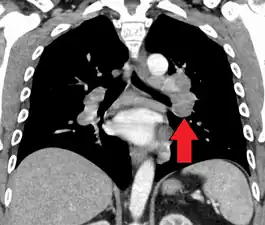

- Hilar adenopathy especially on the person's left (AP CXR)

- Hilar adenopathy especially on the person's left (coronal CT)